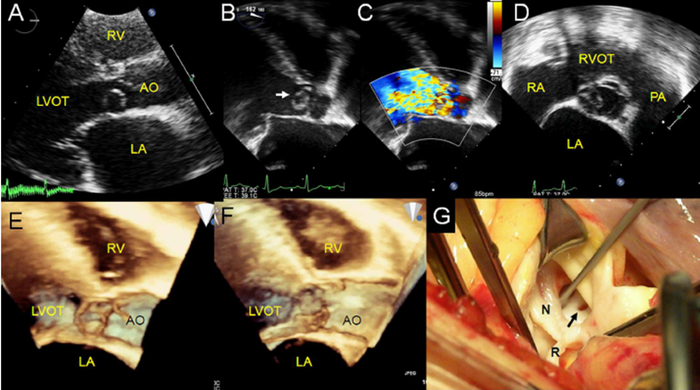

疑难重症心血管疾病超声精准诊断方法及临床应用

主要完成人:谢明星,张丽,王新房

疑难心血管病诊断困难,病情危重,进展迅速,死亡率高。其早期诊断与及时干预,一直是全球心血管疾病防控中的重大课题。团队针对不同类别疑难病种与病例,提出了超声准确诊断方法与分型诊断流程,建立了心房、心室功能早期改变的多参数评估方法,显著提高了心血管超声对疑难心血管病病理结构评估和功能评价的准确性。

▲罕见主动脉窦瘤破入左室流出道。经胸联合经食道超声显示主动脉瓣环附近囊性病变(白色箭头)、形变和动度、起源等诊断主动脉窦瘤,通过瘤体脱入左室、瓣环和窦壁分离等个性特征确定其亚型,并被手术证实。